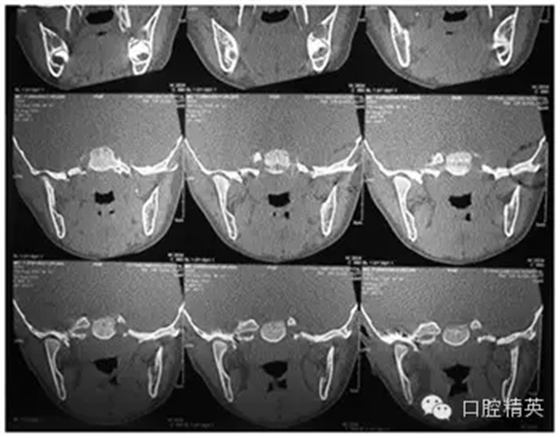

CT

圖